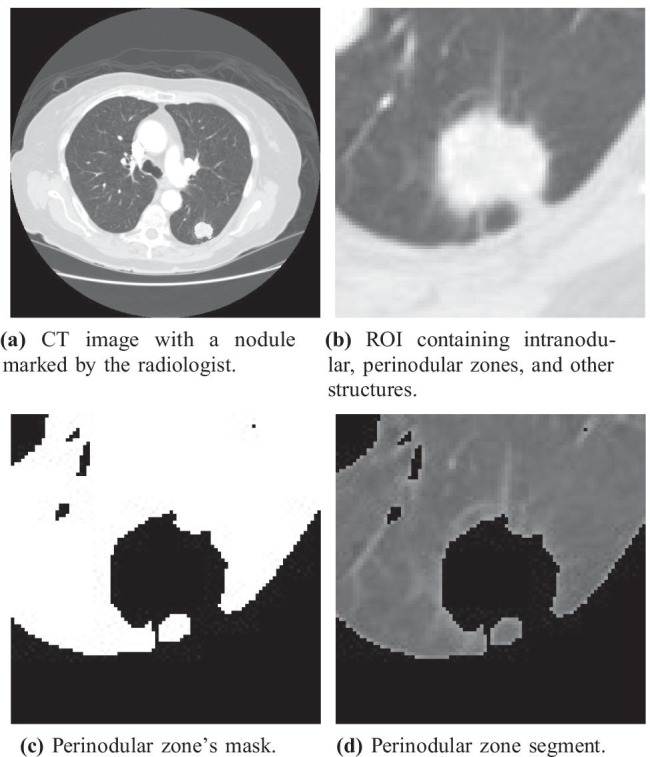

To improve the accuracy and consistency in the medical image diagnosis, the computer-aided diagnosis tools (CADx) and radiomics tools have been providing support to the radiologist’s decision, acting as a second opinion [18, 19]. The medical image community has been advancing the CADx area, proposing innovative algorithms that are more robust, precise, and efficient than the early CADx systems [29, 32, 34]. Nowadays, a widely used approach for CADx and radiomics is based on the segmentation and extraction of quantitative attributes from diagnosed nodule images; these attributes are used for clinical decision support by training machine learning algorithms to classify unknown nodule samples [11, 17, 27]. In general, these works converged on the development and analysis of attributes that best describe a region of interest, i.e., the intranodular zone (Fig. 1a), focusing on the radiomic characteristics of shape, edge, and texture of the nodule [14, 18, 39].

Fig. 1.

(a) shows the intranodular zone of a malignant lung nodule and (b) shows the parenchyma region that surrounds the nodule, also called the perinodular zone

Nevertheless, according to Beig et al. [10] the perinodular zone (Fig. 1b) or habitat of a malignant lesion may exhibit different molecular, radiological, or cellular alterations than the perinodular zone of a benign lesion. Therefore, as perinodular zone has relevant information about the nodule’s nature, some authors [3, 15, 36] have applied radiomic attributes and machine learning to recognize patterns of malignancy and classify lung nodules using the perinodular zone.